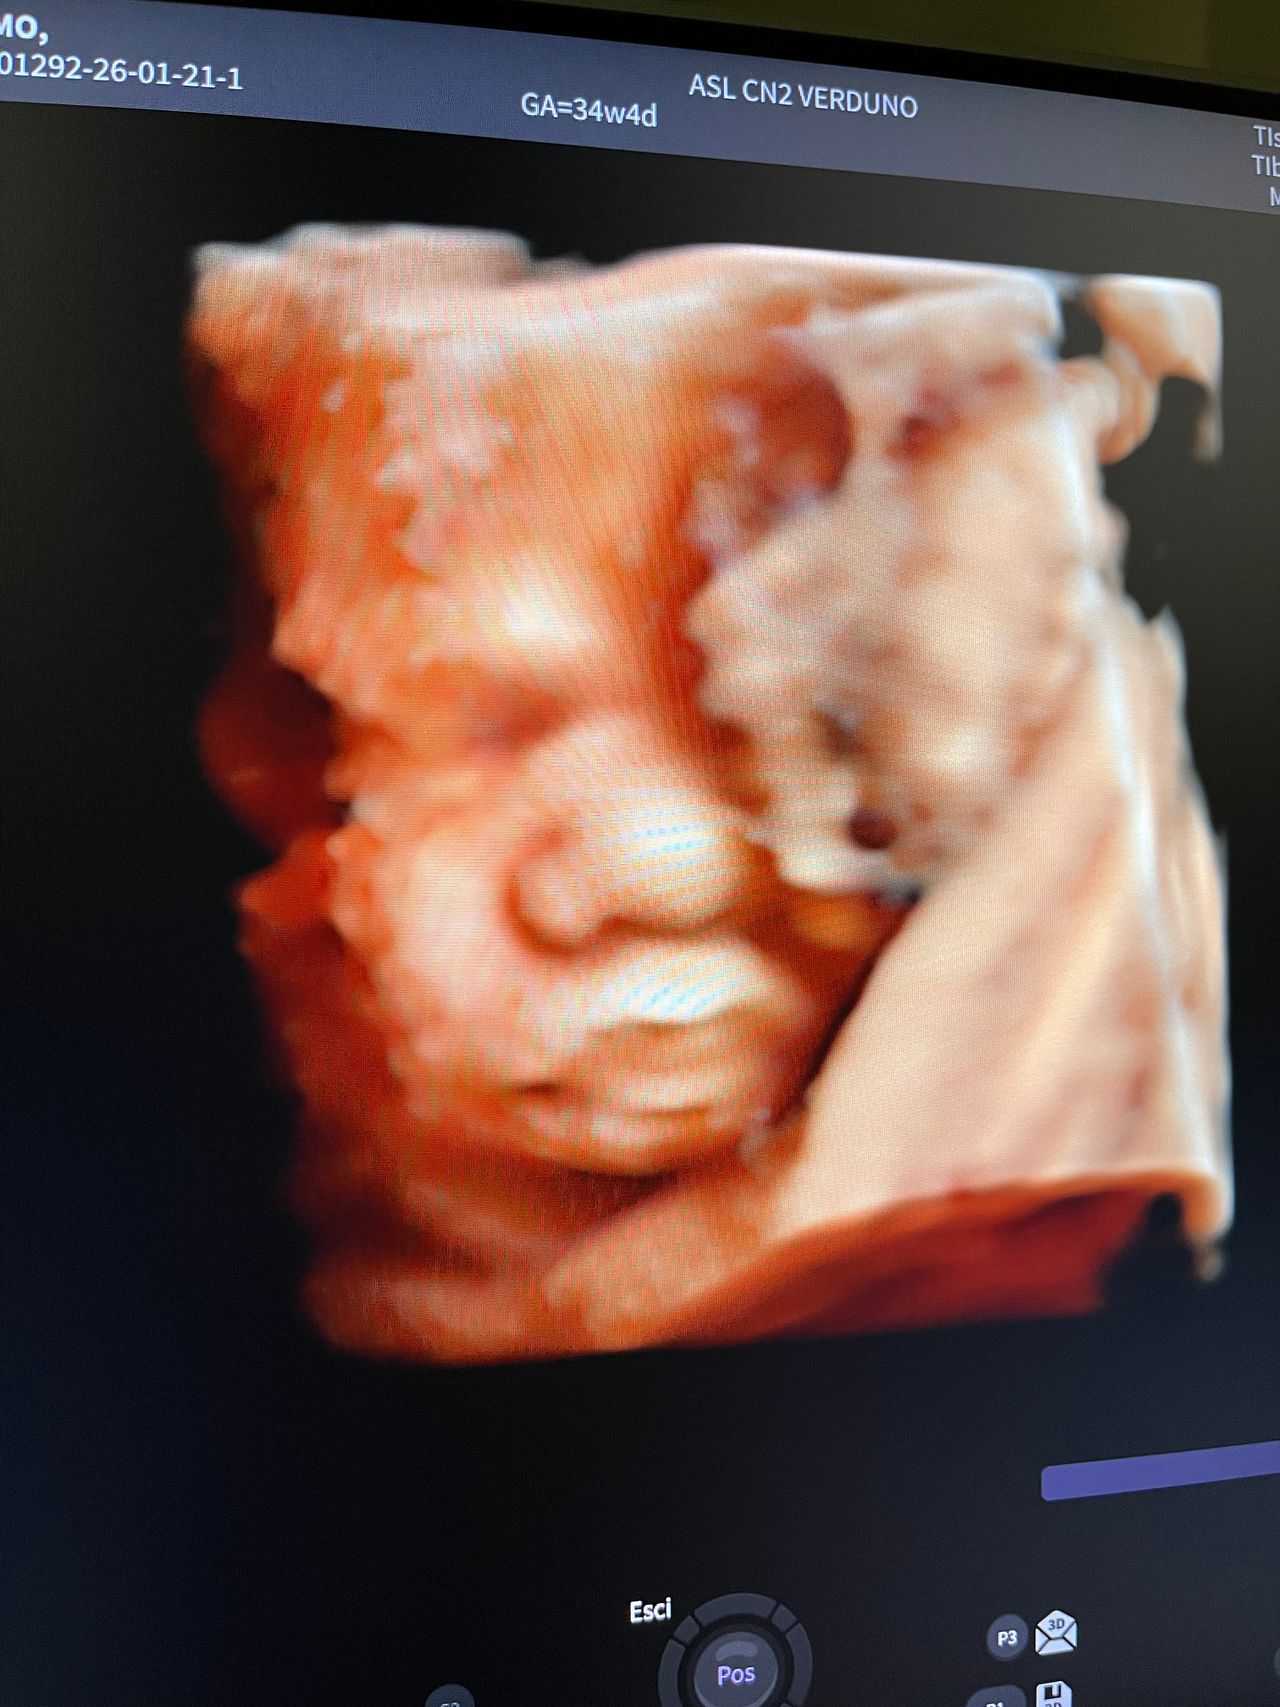

Attualmente lavoro come Dirigente medico nella SC di Ostetricia e Ginecologia dell'Ospedale Michele e Pietro Ferrero di Verduno, mi occupo prevalentemente di screening prenatale, ecografia ostetrica del I trimestre( misurazione translucenza nucale,NT), ecografia morfologica del II trimestre, ambulatorio pregresso taglio cesareo, ecografia ostetrica 3D. Seguo le gravidanze fisiologiche e quelle ad alto rischio , presto servizio in sala parto. Eseguo visite ginecologiche di I-II livello in regime ambulatoriale, counseling contraccettivo ed eventuale prescrizione pillola, inserimento spirale (IUD), dispositivo sottocutaneo (Nexplanon).

Foto e video